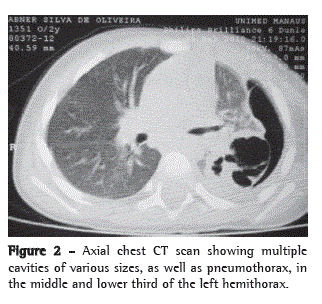

The most common postoperative complication was persistent air leak through a BPF, which occurred in 4 patients (20%), all of whom had undergone segmentectomy. The other complications were as follows: pneumatocele, in 1 patient (5%); empyema, in 1 (5%); and phlebitis of the left arm, in 1 (5%). There were 9 patients (45%) who had no postoperative complications and were discharged, on average, on postoperative day 10 (Table 2). Figures 1, 2, and 3, respectively, show the radiographic, tomographic, and surgical findings in 1 patient submitted to resection of segment VI.

Chest pain, signs of respiratory distress, persistent fever, a worsening of the clinical status, and new complications secondary to pneumonia despite the use of optimal antibiotic therapy are all suggestive of pulmonary necrosis.(6,8,9) In patients meeting any of those criteria, axial chest CT is indicated, even if chest X-rays reveal no abnormalities, since chest X-rays have low sensitivity and early findings characteristic of necrotic complications are rare.(8-10) The most characteristic axial chest CT findings in NP are areas of lower density and multiple cavities, with or without air-fluid level, that can coalesce and form a single, extensive cavity.(10,11) In the present study, all of the patients underwent axial chest CT, and the most common finding was multiple cavities. In 75% of the patients, these cavities were seen on chest X-rays taken before axial CT.